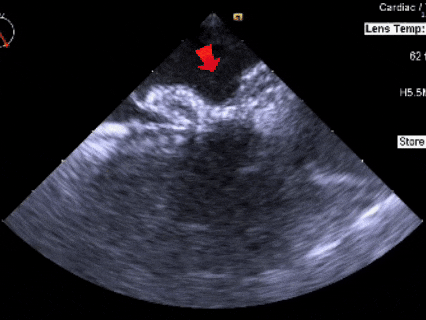

释放

超声下可见封堵器形态良好,封堵成功

释放后评估

彩色多普勒血流成像显示无残余分流存在

封堵成功

释放后多切面下观察

封堵器位置正确、形态良好